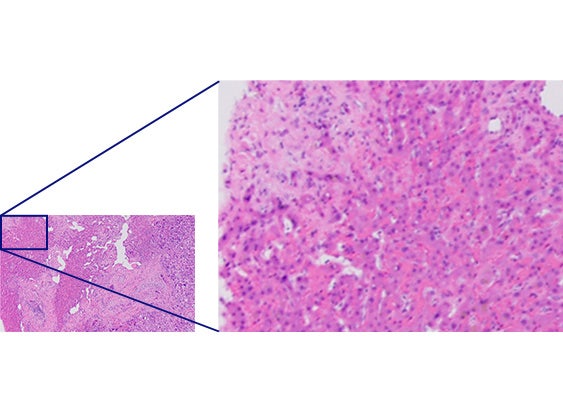

Comparaison de la résolution

Objectifs conventionnelsX Line

Qualité uniforme du centre jusqu'au bord

L'amélioration de la planéité produit des images de qualité supérieure et uniforme, du centre jusqu’au bord. La grande ouverture numérique (NA) permet aux objectifs de capter plus de lumière pour produire des images plus lumineuses et de plus haute résolution. Le couplage des objectifs X Line avec un microscope droit BX53 améliore la qualité globale des images.